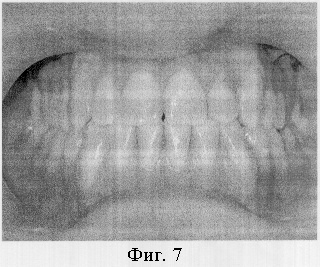

Под местной анестезией проведена остеотомия во всю толщу альвеолярных частей обеих челюстей над корнями передних зубов. Установлены стальные дуги 0,17×0,25 (паз брекета – 0,18) с реверсионными изгибами. Спустя неделю начаты активации реверсионных изгибов на дугах (фиг.6). Через 2,5 месяца после операции достигнут ортогнатический прикус (фиг.7).

Через полгода после снятия ортодонтической аппаратуры прикус стабилен. Пациент пользуется несъемными ретейнерами.